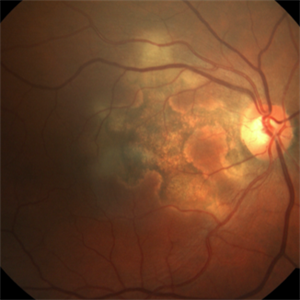

66-year-old woman with acute visual acuity loss.

Photographer: Claudio Zett Lobo, UNIFESP

Condition/keywords: acute syphilitic posterior placoid chorioretinitis